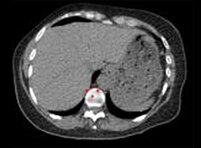

-product-categories-nuclear-medicine-spect-ct scanners-discovery 670 new-smallerimage1.png

4 切片,650 mAs CTDIvol = 2.98 mGv DLP = 125.1 mGv x cm 有效剂量 = 1.75 mSv * *由 ICRP 获得,使用成人胸部因子 0.014 * DLP

Optima NM/CT 640

-product-categories-nuclear-medicine-spect-ct scanners-discovery 670 new-smallerimage2.png

4 切片,460 mAs CTDIvol = 2.01 mGv DLP = 56.6 mGv x cm 有效剂量 = 0.79 mSv*